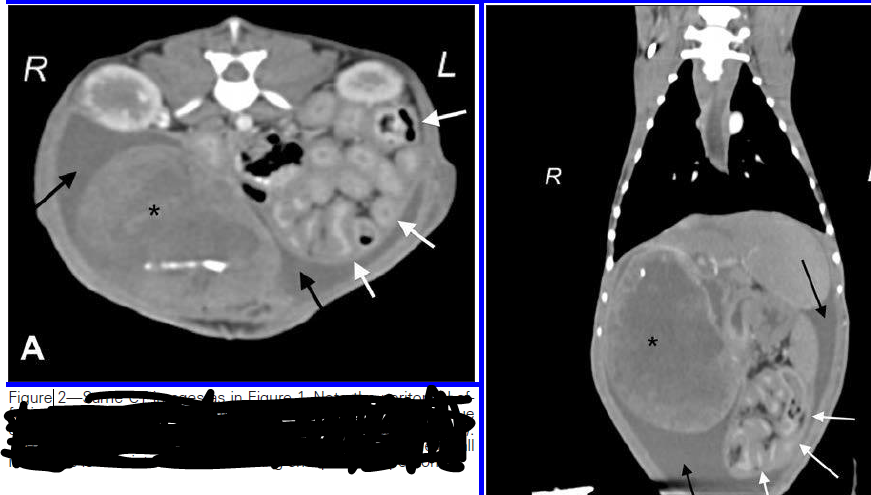

Adult feline presented for abdominal pain and dragging rear limbs.

Multiple filling defects of the arterial system, including abdominal aorta, bilateral large infarcts to the kidneys as no contrast is present within them and cranial mesenteric artery.

Imaging diagnosis - Acute mesenteric ischemia secondary to HCM in a cat - VRU 56.4

Adult cat presenting for abdominal pain and dragging rear limbs.

Portal venous gas within the liver

Peritoneal free gas

Gas within the mesenteric arteries

Severely distended, thin walled bowel loops

Imaging diagnosis - Acute mesenteric ischemia secondary to HCM in a cat - VRU 56.4.